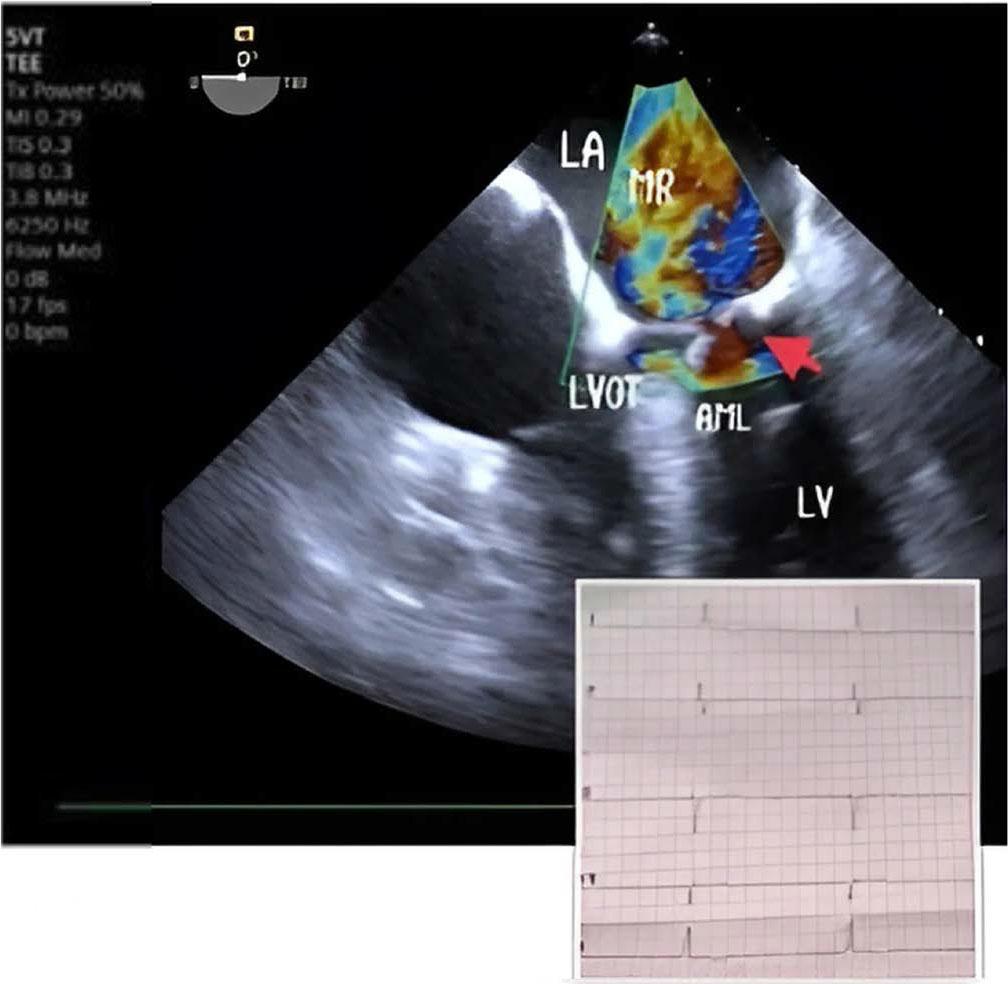

Upon admission to our hospital, the patient was experiencing severe respiratory failure and was promptly transferred to the intensive care unit (ICU). Oxygen saturation levels fell to 50% despite ventilation support through a face mask. Given this critical condition, the decision was made to intubate the patient for mechanical ventilatory support. Unfortunately, even with this support, oxygen saturation did not improve, although blood pressure stabilized at an acceptable level of 100/60 mmHg. Due to a poor transthoracic echocardiogram (TTE) window, a transesophageal echocardiogram (TEE) was performed, which SAM of the mitral valve with severe mitral regurgitation (MR). Figure 2 Pressure gradient across the LVOT was 50 mmHg and the basal interventricular septum thickness was 12,5 mm. No segmental or global wall motion abnormalities were observed.

Severe mitral regurgitation in junctional rhythm. MR mitral regurgitation, LA left atrium, LV left ventricle, LVOT left ventricular outflow tract, AML anterior mitral leaflet